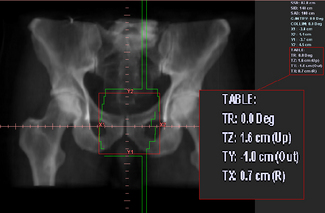

The treatment planning portion of the CT simulation process starts with the definition of a treatment reference point that can either coincide exactly with the position of the isocentre or alternatively can be an estimate of its position. The former method will require the definition of the target volume to define precisely the treatment isocentre and will require the oncologist to be present; whereas the latter method does not require the target volume to be defined and the final isocentre position can be found using ‘shift coordinates’. These shift distances,Figure 9.7 are relative to the reference point and can be applied at the first treatment in order to align precisely the isocentre to the target. The shift coordinate method is commonly used in a busy department where there is limited time to wait until targets are contoured or where the oncologist is not available during the scanning session.

image

Figure 9.7 BEV/DRR with shift information.

Shift coordinates’ are printed from the relationship between the isocentre to ‘patient reference origin’ coordinates. These are transferred to the treatment machine with the plan details. Worksheets and DRRs are printed (see figure 9.7).